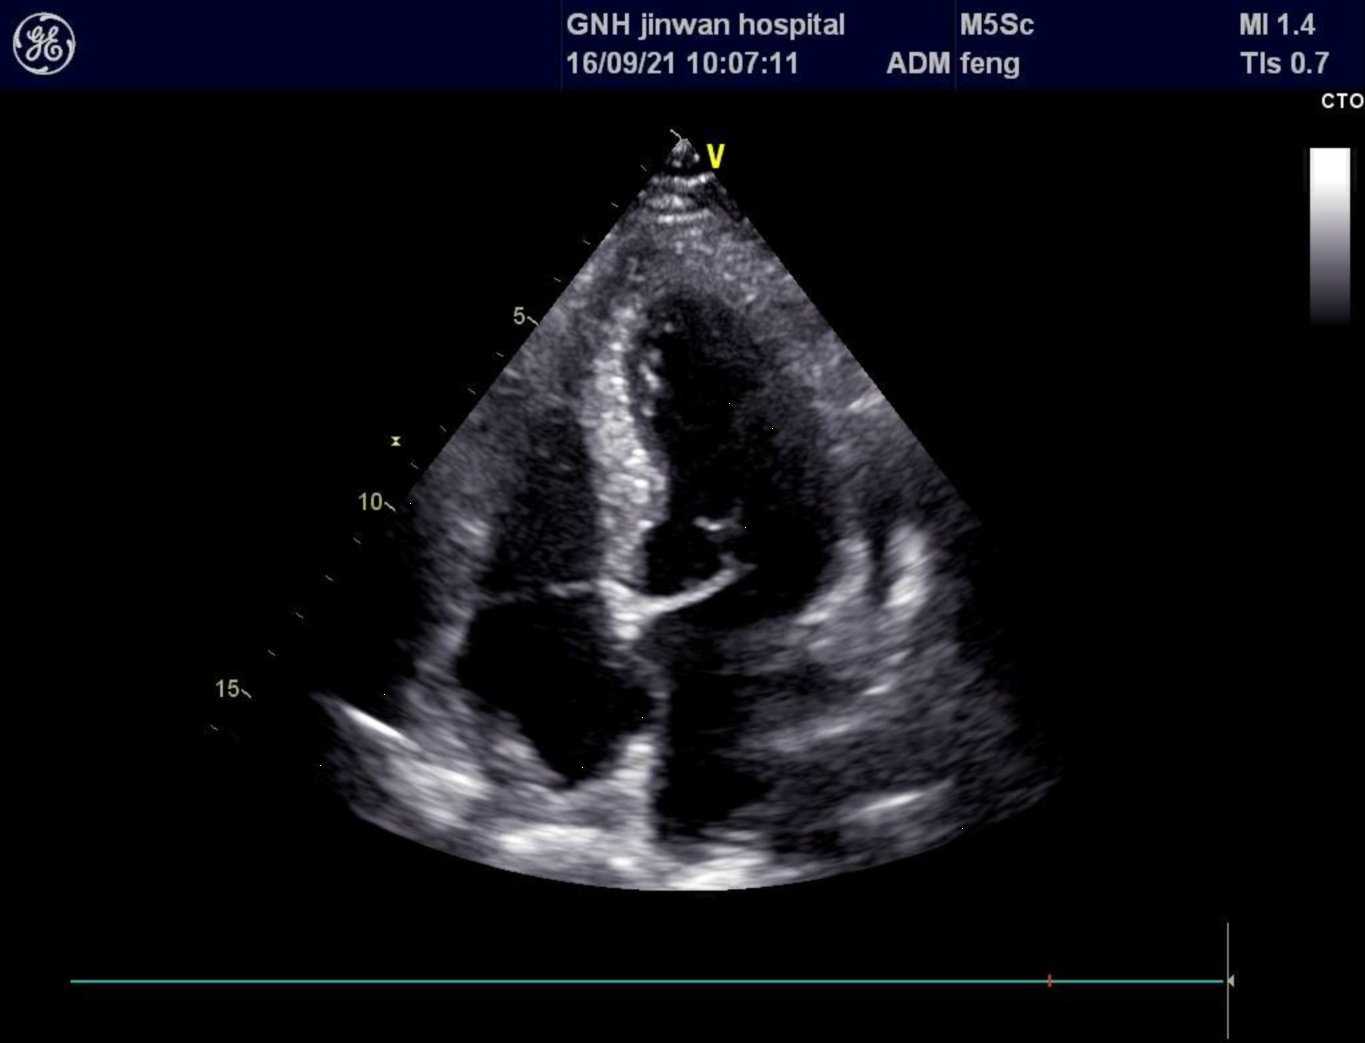

手術過程很順利,術中切下來的腫塊病理結果證實腫瘤類型的確為脂肪瘤。術後李伯伯恢復良好,第四天就從ICU轉回了普通病房,不久之後就康復出院了。從發現瘤子,到出院不過20天,術後傷口大小不到4cm。

術後的心臟彩超影像